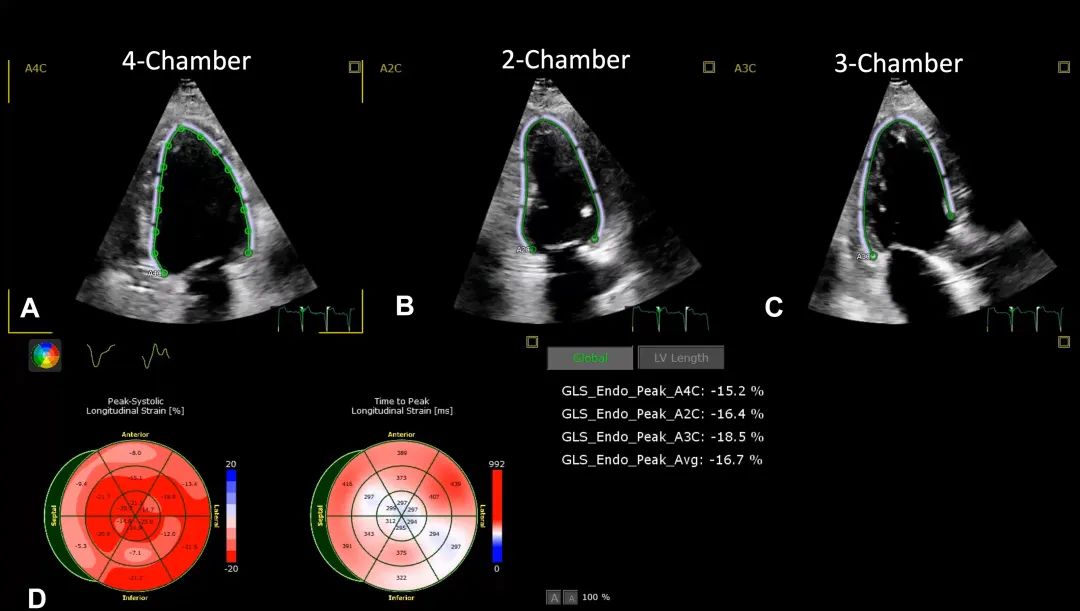

6、心尖四腔心切面: 评估左室射血分数(二维和/或三维)及左室整体纵向应变(global longitudinal strain,GLS)。需注意的是,评估左室整体纵向应变必须同时获得心尖四腔心、二腔心和三腔心视图(图7,视频4)。

图7. 左室整体纵向应变

利用四腔心切面(A)、二腔心切面(B)和三腔心切面(C)进行左室应变评估。这些图像经分析后,以靶心图形式(D)显示节段性纵向应变。